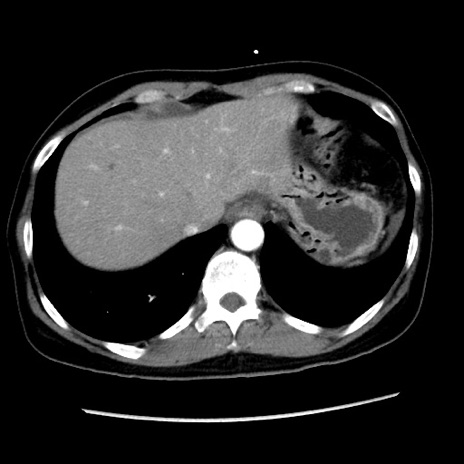

症例10(横断像)

【症例】 50歳代女性

【主訴】 腹痛

【現病歴】前日生レバーを食べた。今朝に排便あり。 昼前に突然発症の腹痛を生じ、当院救急外来を受診した。

【身体所見】 意識清明、腹部:平坦、軟、下腹部やや左を中心に圧痛・反跳痛あり、筋性防御あり

【データ】WBC 7800、CRP 0.07